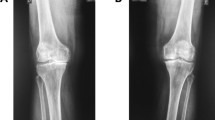

The study employed a two-arm parallel-group randomized comparative design. In this study, females (n = 60) diagnosed with grade II knee OA according to the Kellgren-Lawrence (KL) scale13 were randomized into two groups: Group 1 was assigned to perform knee strengthening exercises (n = 30), and Group 2 was assigned to perform both knee strengthening exercises and exercises based on polyvagal theory to stimulate the vagal nerve (n = 30).

Ninety-four patients with complaints of knee pain underwent screening for grade II knee OA. However, thirty-four patients were excluded during the initial eval‎uation because they did not meet the inclusion criteria. The remaining 60 patients were randomly allocated into two intervention groups (with each group consisting of 30 patients): Group 1 performed only knee strengthening exercises, and Group 2 performed both knee strengthening exercises and polyvagal theory–based exercises. Randomization was performed at a 1:1 allocation ratio using sealed envelopes. Figure 1 illustrates the study procedures comprehensively through a CONSORT (2010) flow chart, outlining key stages such as assessment, enrollment, randomization, intervention allocation, follow-up, and data analysis.

무작위 배정은 밀봉된 봉투를 사용하여 1:1 배정 비율로 수행되었습니다. 그림 1은 평가, 등록, 무작위 배정, 중재 배정, 추적 관찰, 데이터 분석과 같은 주요 단계를 개요로 제시하는 CONSORT(2010) 흐름도를 통해 연구 절차를 종합적으로 보여줍니다.

Figure 1

A CONSORT (2010) flow chart of the study design.

그림 1

연구 설계의 CONSORT(2010) 흐름도.